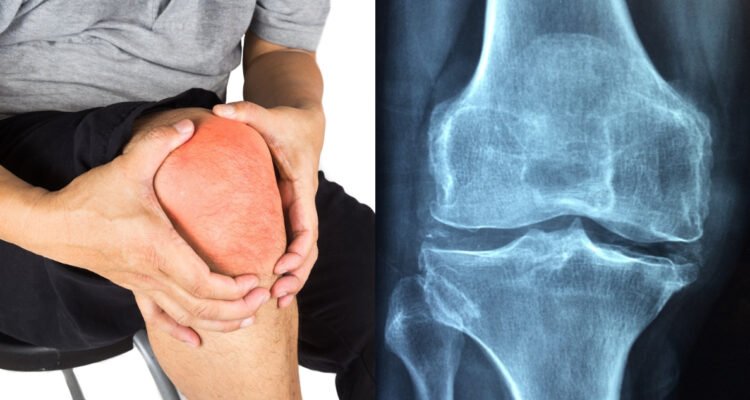

La osteoartritis es la forma más común de artritis y una de las principales causas de dolor crónico y discapacidad en adultos: se espera que para el año 2050 más de mil millones de personas en todo el mundo se vean afectadas por esta enfermedad, según cifras del Instituto para la Métrica y la Evaluación de la Salud (IHME por sus siglas en inglés).

En Chile la realidad es bastante similar. La Encuesta Nacional de Salud 2016-2017 realizada por el Ministerio de Salud estimó que más del 50% de la población mayor de 50 años sufre de artrosis en alguna articulación relevante, siendo la más común en rodilla.

Este innovador tratamiento cuenta con pruebas de laboratorio y con una primera validación humana en una mujer chilena con osteoartritis, quien se convirtió en la primera paciente a nivel mundial que recibe este tratamiento para combatir artrosis de rodilla, obteniendo excelentes resultados.

Los investigadores apuntan a las propiedades regenerativas y antiinflamatorias de las vesículas extracelulares pequeñas estudiadas en laboratorio. Los resultados apuntan al potencial regenerativo del cartílago hialino y retención localizada en la articulación de la rodilla, alcanzando significancia estadística en múltiples resultados primarios y secundarios.